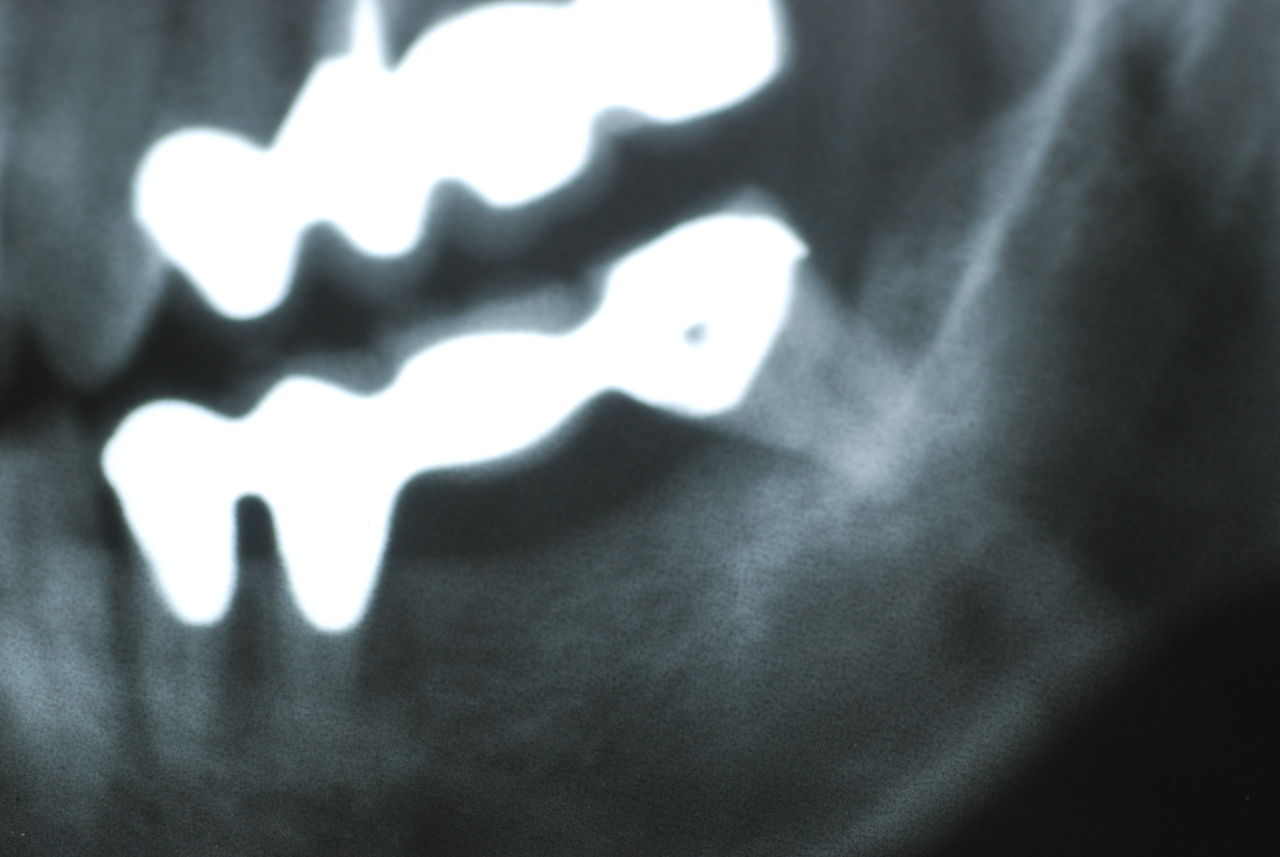

隣の14歳大臼歯がひどい虫歯になり治療不可能になりつつある状態のレントゲン

レントゲンでは小さいですが、こう言う虫歯が一番怖いのです。

治療の成功率は極めて悪くすぐ再発しやすいのです。